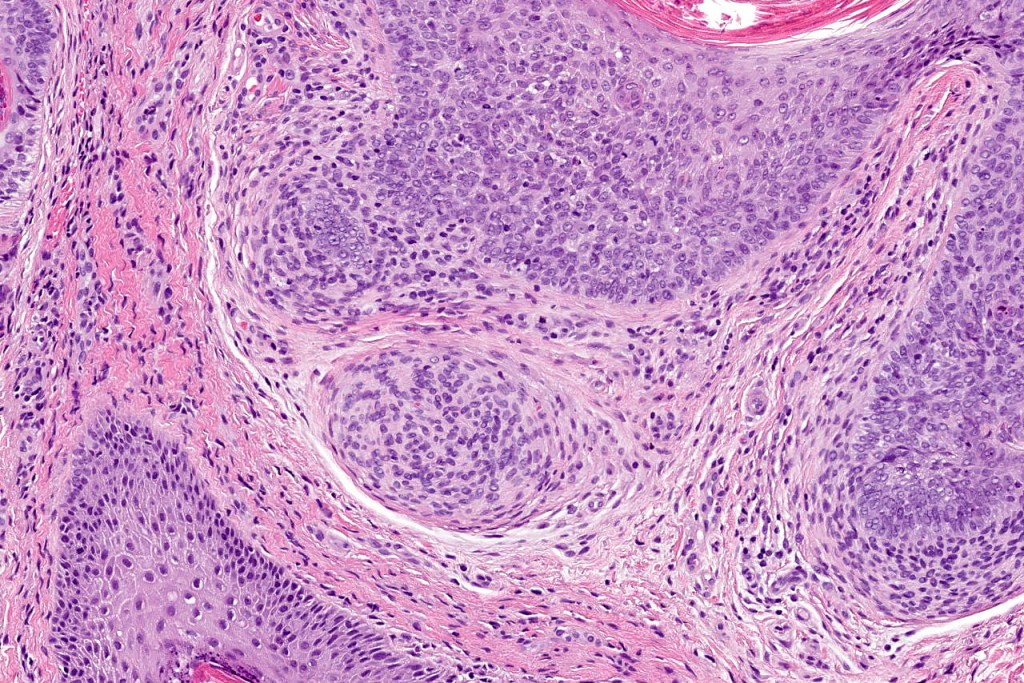

•The classical appearance consists of keratocysts & lobules of basaloid cells

•Basaloid lobules show peripheral palisading

•Retraction artifact and mucin deposition as seen in BCC are not present

•Perifollicular mesenchyme is always conspicuous and sometimes densely aggregated are seen indenting the baslaloid lobules (papillary mesenchymal bodies)

Trichoepithelioma should be distinguished from trichoblastoma since the latter is very rarely syndromic. Trichoepithelioma is largely a dermal tumor whereas trichoblastoma often extends from the dermis into subcutaneous fat or deeper in very large examples. Papillary mesenchymal bodies are much better formed and generally more obvious in trichoepithelioma. Trichoepithelioma must also be distinguished from basal cell carcinoma. Retraction artifact & stromal mucin are features of basal cell carcinoma and not trichoepithelioma. Papillary mesenchymal bodies are not seen in basal cell carcinoma.